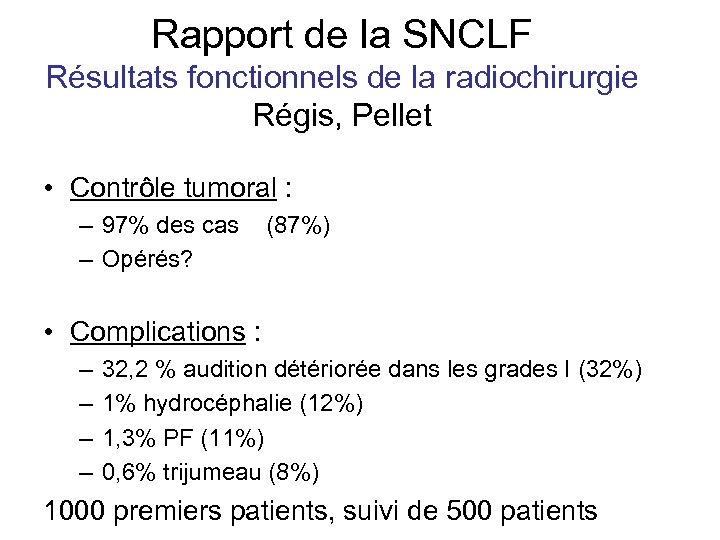

Rapport de la SNCLF Résultats fonctionnels de la radiochirurgie Régis, Pellet • Contrôle tumoral : – 97% des cas – Opérés? (87%) • Complications : – – 32, 2 % audition détériorée dans les grades I (32%) 1% hydrocéphalie (12%) 1, 3% PF (11%) 0, 6% trijumeau (8%) 1000 premiers patients, suivi de 500 patients

Rapport de la SNCLF Résultats fonctionnels de la radiochirurgie Régis, Pellet • Contrôle tumoral : – 97% des cas – Opérés? (87%) • Complications : – – 32, 2 % audition détériorée dans les grades I (32%) 1% hydrocéphalie (12%) 1, 3% PF (11%) 0, 6% trijumeau (8%) 1000 premiers patients, suivi de 500 patients